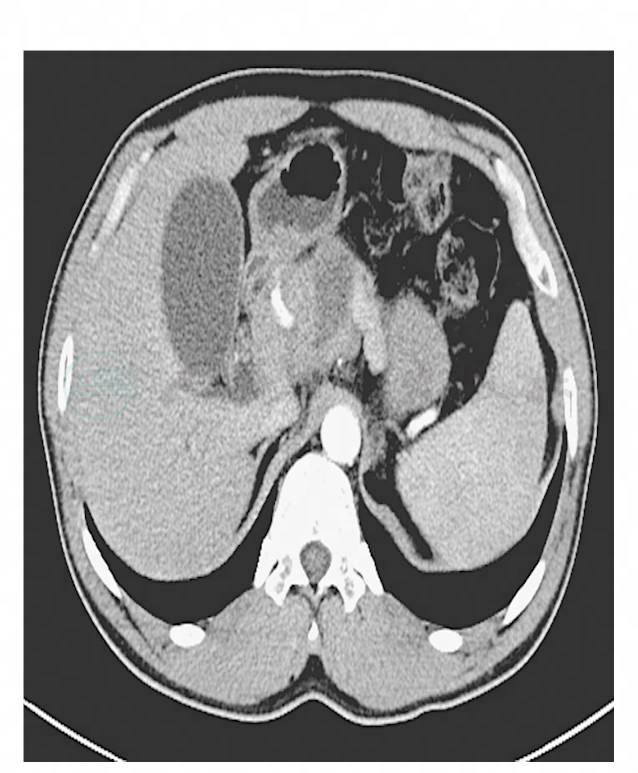

血清总胆红素2.3mg/dl(正常值0.2~1.2mg/dl),结合胆红素1.6mg/dl(正常值0~0.5mg/dl),γ-谷氨酰胺转肽酶1194.1U/L(正常值9~64U/L),肿瘤标记物CA19-9和CEA正常,血常规及血淀粉酶正常。胸片未发现肺内异常,腹部CT发现胰颈附近6.4cm×3.8cm肿物,形状不规则,内部局灶低密度改变,增强后未见明显强化。胆囊略增大,肝内胆管可见扩张(图1)。

图1 腹部CT示胰颈肿物,形状不规则,增强后未见明显强化